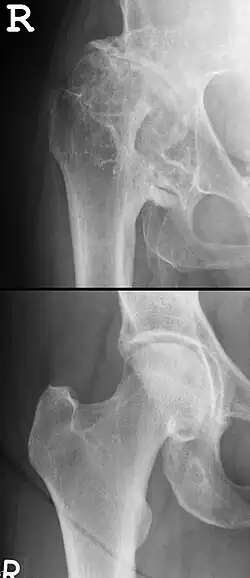

Die Diagnose der Hüftgelenksarthrose erfolgt anhand von Röntgenbildern, die in der Regel sehr aussagekräftig sind und eine genaue Stadieneinteilung der Krankheit erlauben.

Radiologische Diagnostik

Für die Diagnostik einer Hüftgelenksarthrose ist normalerweise eine röntgenologische Untersuchung ausreichend. Gewöhnlich werden Röntgenaufnahmen in zwei Ebenen durchgeführt:

- die Aufnahme im a.p.-Strahlengang (im Liegen oder im Stehen) sowie

- die Lauenstein-Aufnahme (im Liegen), die vor allem der seitlichen Darstellung des proximalen Oberschenkelknochens dient.

Durch die oben aufgeführten Aufnahmemethoden sind in der Regel alle radiologischen Zeichen der Coxarthrose darstellbar.[7][16] Diese sind:

- Gelenkspaltverschmälerung: anfänglich im Hauptbelastungsbereich, breitet sich in der Folge über den gesamten Gelenkspalt aus

- Geröllzysten: werden besonders kranial der Hüftpfanne groß und verursachen die Inkongruenz der Gelenkfläche

- subchondrale Sklerosierung: besonders die Hüftpfanne ist betroffen

- Osteophyten: besonders lateral-kranial und medial-kaudal an der Hüftpfanne (Azetabulum); seltener am Oberschenkelknochenkopf („capital drop“)

Die radiologischen Zeichen der Coxarthrose sind zwar zuverlässig (Sensitivität 89 %, die Spezifität 91 %),[17] müssen allerdings nicht mit dem Ausmaß der Hüftbeschwerden und mit dem klinischen Befund korrelieren.

Das Röntgenbild kann auch Auskunft über präarthrotische Deformitäten, beispielsweise bei einer Hüftdysplasie (vgl. Abb.) als Ursache der Coxarthrose geben.[18] Hier ist der Hüftkopf nicht ausreichend überdacht und steht deswegen dezentriert nach oben / seitlich heraus. Dadurch resultiert eine Verkürzung der Beinlänge. Im Laufe der Zeit kommt es zu einer massiven „Entrundung“ des Hüftkopfes, der Gelenkspalt ist fast ganz aufgehoben, das Hüftgelenk wird steif.